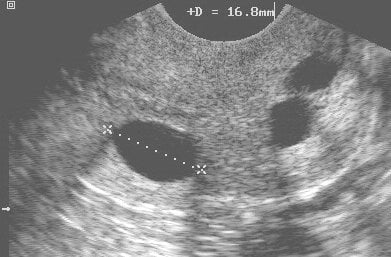

Serviks kanalı normalde mukus salgılayan ve Naboth adı verilen salgı bezleri ile döşenmiştir. Bu salgı bezlerinin dışarıya açılan ağızları metaplazi adı verilen normal bir süreç neticesinde normal hücre tabakası ile kaplanır ve tıkanır. Bu değişimin sonucunda Naboth bezlerinin salgısı dışarıya akamaz ve bez şişmeye başlar. Salgı biriktikçe bez genişlemeye başlar ve rahim ağzı üzerinde yüzeyden kabarık küçük ksitik bir oluşum halini alır. Muayenede yüzeyden kabarık soluk renkli kabarcıklar olarak görülür. Ultrason incelemesinde fark edilebilir. Kistler tek ya da gruplar halinde birden fazla sayıda olabilir.

Tanı başka bir şikayet nedeniyle yapılan ya da rutin muayene sırasında konur. Hemen her zaman normal muayene bulgusu olarak değerlendirilir. Çok nadiren boyutlarının çok büyük ya da görünüşünün alışılmışın dışında olduğu durumlarda kolposkopi ve biopsi gerekebilir.